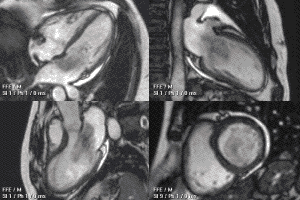

Диагностика митрального стеноза основывается на данных рентгенографии, электрокардиографии, эхокардиографии, катетеризации камер сердца.

- Эхокардиография. Обнаруживает уплотнение стенок митрального клапана и уменьшение площади митрального отверстия;